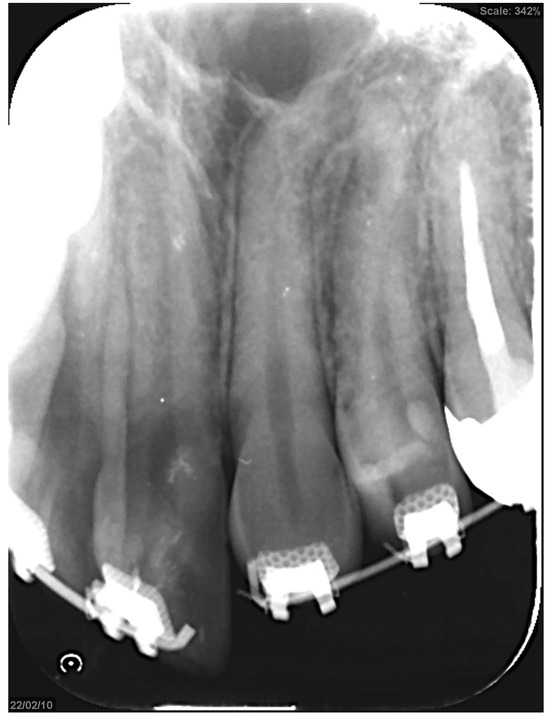

3.3. Panoramic Cephalometric Radiograph (Figure 2A)

In the maxilla, the right first premolar, second molar, and left second premolar had undergone root canal treatment. Similarly, in the mandible, the right second premolar, first molar, and left second molar also underwent root canal treatment. An apical lesion was observed in the mandibular left second molar. Notably, wisdom teeth were present in the left maxillary and right mandibular regions. However, there was minimal curvature of the teeth roots, and the alveolar bone level appeared normal throughout the dentition.